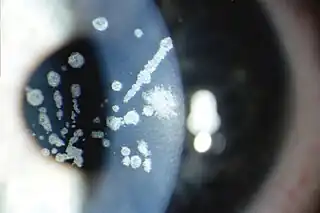

![]() Opacidades en la córnea en la distrofia corneal de Avellino | ||

Los síntomas que provoca son depósitos en la capa de la córnea llamada estroma, por lo que esta pierde su transparencia, ocasionando perdida de visión. En muchas ocasiones el tratamiento recomendado es un trasplante de córnea, pero los depósitos pueden volver a producirse ocasionando de nuevo un deterioro de la visión.